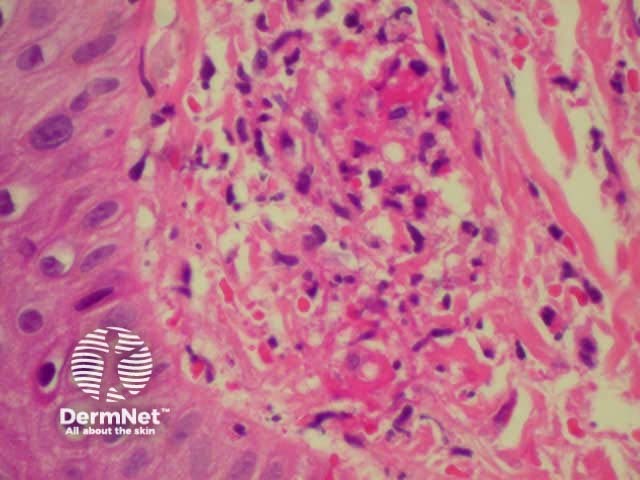

Dermatopathology shows a necrotising vasculitis.

Dermatopathology of hypersensitivity vasculitis